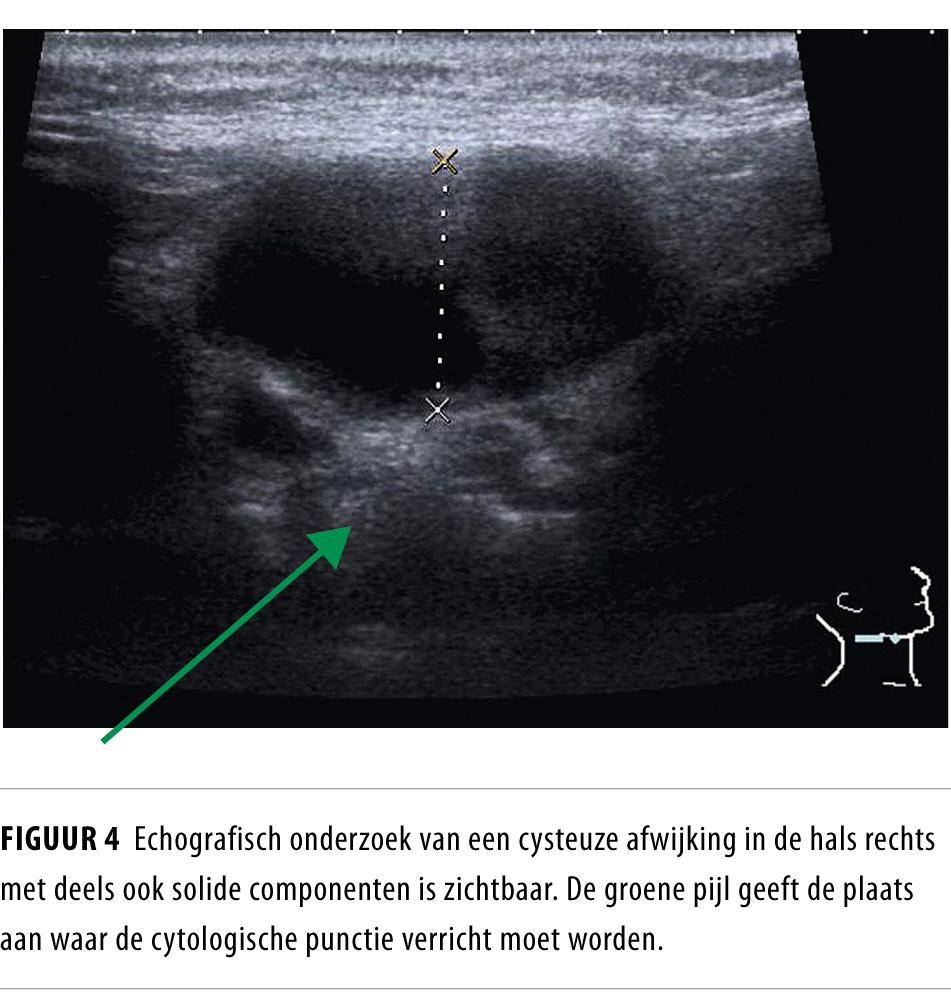

Een cysteuze zwelling in de hals bij volwassen patiënten is meestal een laterale halscyste, maar kan ook een lymfekliermetastase van een primaire tumor in het hoofd-halsgebied zijn. Oplettendheid is met name geboden bij patiënten ouder dan 40 jaar en met risicofactoren als nicotinegebruik en alcoholabusus. Een lymfekliermetastase moet worden uitgesloten voordat de afwijking abusievelijk als laterale halscyste wordt behandeld.

Het is bekend dat lymfekliermetastasen van plaveiselcelcarcinomen uitgaande van de mucosa van de ring van Waldeyer (nasofarynx, tonsillen, tongbasis) een cysteuze verandering kunnen ondergaan en kunnen imponeren als een laterale halscyste.1 De kans dat een cysteuze zwelling in de hals bij patiënten ouder dan 40 jaar berust op een metastase van een hoofd-halstumor is circa 25%.2 In de praktijk blijkt het onderscheid moeilijk.